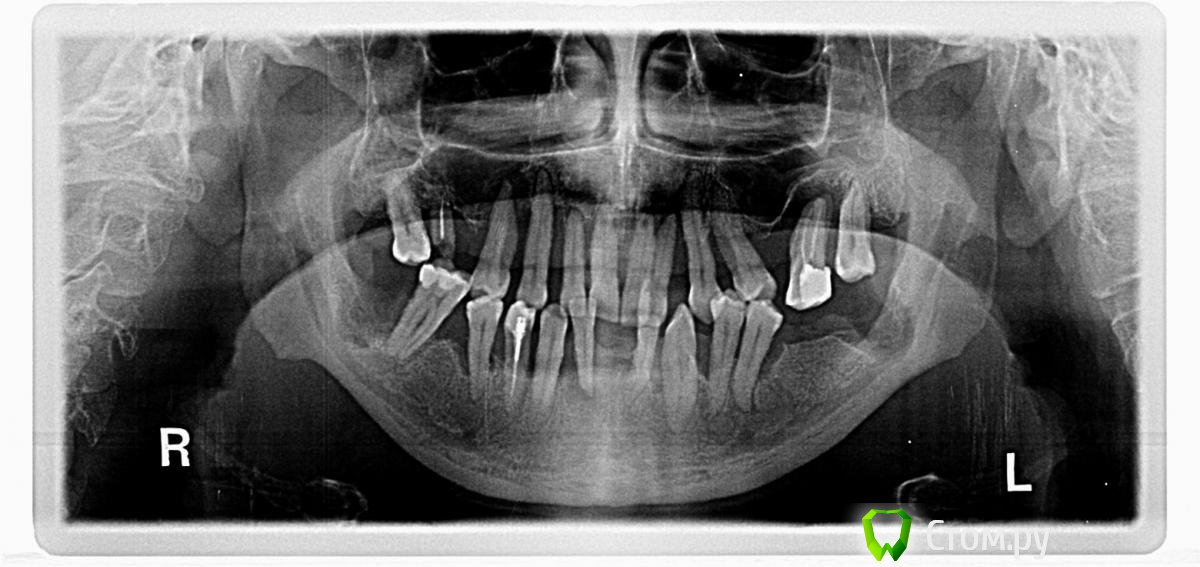

OldFox Опубликовано 26 ноября, 2014 Поделиться Опубликовано 26 ноября, 2014 (изменено) Уважаемые специалисты, очень прошу дать совет как поступить с зубами.Мне - 45. На учетах у врачей не состою, снял ортопантомограмму и сдал анализы крови(похоже, что всё в норме чуть больше гемоглобина).Зубами - парадонтитом - очень плотно занимался несколько лет, но потом опустились руки -ничего не помогало... и довольно долго не обращался к врачам вообще. Сейчас ситуация следующая - впереди внизу старенький пластиковый сьемный протез, но правый резец под ним - уже еле держится.Недавно потерял снизу две восьмерки - просто начали качаться и выпали (не удалял).Из 20 оставшихся зубов некачаются:правые 23, 24 и двух самых последних с обоих сторон (я могу ошибаться 18 и 28 помоему называются).Все остальные сверху так или иначе подвижны - особенно передние резцы.Внизу качается только правый резец под протезом (42) и совсем чуть уже левая четверка.Зубы хоть и совсем не болят, но некоторые достаточно сильно оголились. Понимаю, что точка невозврата уже пройдена довольно давно, и свои зубы уже не спасти,очень прошу дать совет, что можно сделать с достаточно скромным бюджетом(200-250т.р.).Возможно в нашем регионе, но если нет 'наших' на форуме, то можно рассмотреть вариант с Питером - там учился и есть где остановиться. Проконсультировался в двух наших частных городских клиниках, получил примерно одинаковые советы, с небольшими ньюнсами.В одной:- удалять практически все передние сверху, оставить возможно некачающийся клык и восьмерки- снизу, как сказал врач, по мере удаления смотреть что можно оставить(возможно оба клыка, может чтото еще)+ сьемное протезирования после заживления на верх и низ (плавающий нижний, если честно, очень напрягает)Во второй: - сверху удалять всё - снизу тоже бы нужно всё удалять, изза бюджета на текущие 2-3года, оставить клыки и одну из четверок, их все - депульпировать (четверка остается та, которая уже депульпированная - она не качается, возможно ее нужно будет проверить) - и врач говорит, что это очень не надолго. ++ вообще врач предлагал минимум 8 имплантов - сверху (низ пока никак не оговаривали), но как временная мера: + четыре импланта сверху-спереди начиная с клыков - IMPRO® IMPLANTEM (Германия) с временной конструкцией(6 единиц) и замещением на постоянку через 6 месяцев. + снизу на обточенные и депульпированные 3 зуба(44, 43 и 33) - мост из металокерамики из 7 единиц (повторюсь врач с большим сомнением относится к этой конструкции) * поэтому думаю может убрать и эти последнии и поставить 2 импланта снизу - возможно в район клыков и протезироваться на них? Совсем без зубов остаться не могу - работа не позволит. Без жующих оставаться - очень страшно, как собственно и без всех остальных, но люди както живут.Но без временных (см.выше) мер - обойтись пока не могу. На форуме увидел несколько постов про балочные конструкции, по скольку со сьемными протезами уже так или иначе успел столкнуться - может рассмотреть и этот вариант?И есть варианты 4-in-all или 6-in-all (как я понимаю), но тогда видимо схема имплантирования - будет другая? Прикладываю ортопантомограмму. И очень надеюсь на Ваш совет. Изменено 26 ноября, 2014 пользователем OldFox Ссылка на комментарий